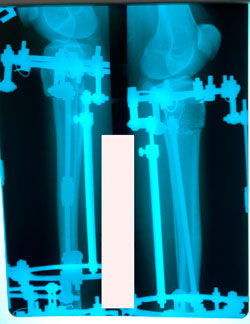

Исходник - 30 лет.

Дата операции - 25.12.2020

Диагноз: варусная деформация + Ротация с обеих сторон.